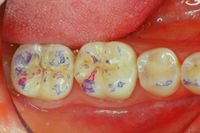

File:Clicker end3.jpg|'''Figure 9c:''' Peculiarities of neurognathological parameters. Occlusal view of the left mediotrusive detail. (work done in 1992)

In figure 9c and 9d, we can see not only the well balanced centric contacts but above all the mediotrusive excursions. A few more words should be spent on this subject. Benedikt Sagl et al.<ref>Sagl B, Schmid-Schwap M, Piehslinger E, Rausch-Fan X, Stavness I. The effect of tooth cusp morphology and grinding direction on TMJ loading during bruxism. Front Physiol. 2022 Sep 15;13:964930. doi: 10.3389/fphys.2022.964930. eCollection 2022.PMID: 36187792 </ref> state, in their study in which the contribution of tooth inclination, medio-otrusive and laterotrusive excursion and von Mises stresses on the articular disc was analysed, that mediotrusive bruxing generates higher loads than laterotrusive simulations. In this sense it is not clear whether the mediotrusive contacts are a protective or a pejorative element in the generation of temporomandibular joint disorders. So much so that an article by Walton TR and Layton DM<ref>Walton TR, Layton DM. Mediotrusive Occlusal Contacts: Best Evidence Consensus Statement. J Prosthodont. 2021 Apr;30(S1):43-51. doi: 10.1111/jopr.13328.PMID: 33783093</ref> increases the confusion as they first state that the presence of TM interference in patient populations is large and varies from 0% to 77% and then conclude that TM interference should be avoided in any occlusal treatment regimen to minimize pulpal, periodontal, structural and mechanical complications or exacerbation of temporomandibular disorders (TMD). The confusion increases when he concludes that natural molar MT interferences should only be eliminated if signs and symptoms of TMD are present. The question that arises is the following

In figure 9c and 9d, we can see not only the well balanced centric contacts but above all the mediotrusive excursions. A few more words should be spent on this subject. Benedikt Sagl et al.[19] state, in their study in which the contribution of tooth inclination, medio-otrusive and laterotrusive excursion and von Mises stresses on the articular disc was analysed, that mediotrusive bruxing generates higher loads than laterotrusive simulations. In this sense it is not clear whether the mediotrusive contacts are a protective or a pejorative element in the generation of temporomandibular joint disorders. So much so that an article by Walton TR and Layton DM[20] increases the confusion as they first state that the presence of TM interference in patient populations is large and varies from 0% to 77% and then conclude that TM interference should be avoided in any occlusal treatment regimen to minimize pulpal, periodontal, structural and mechanical complications or exacerbation of temporomandibular disorders (TMD). The confusion increases when he concludes that natural molar MT interferences should only be eliminated if signs and symptoms of TMD are present. The question that arises is the following

In figure 9c and 9d the mediotrusive path highlighted with the articulation paper was constructed by calculating the angle determined by the unilateral Root-MEPs which displaces the mandible by about 1/2mm on each side. By programming the Denar joint (figure 10) it was possible to construct an excursion with different angles between the TMJ, molar and canine. This procedure generates a natural path in which the canine guides together with the mediotrusion to protect the TMJ from the masticatory load that exists beyond bruxism.